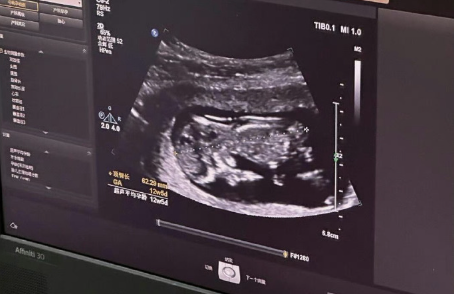

在促排卵期间,医生会通过超声波检查和血液激素水平检测,实时监测卵泡生长情况,以便调整药物剂量和确定最佳取卵时间。这通常涉及多次B超和抽血检查。

移植后需要定期复查,如抽血检查HCG(人绒毛膜促性腺激素)确认是否妊娠,以及后续的B超检查等。